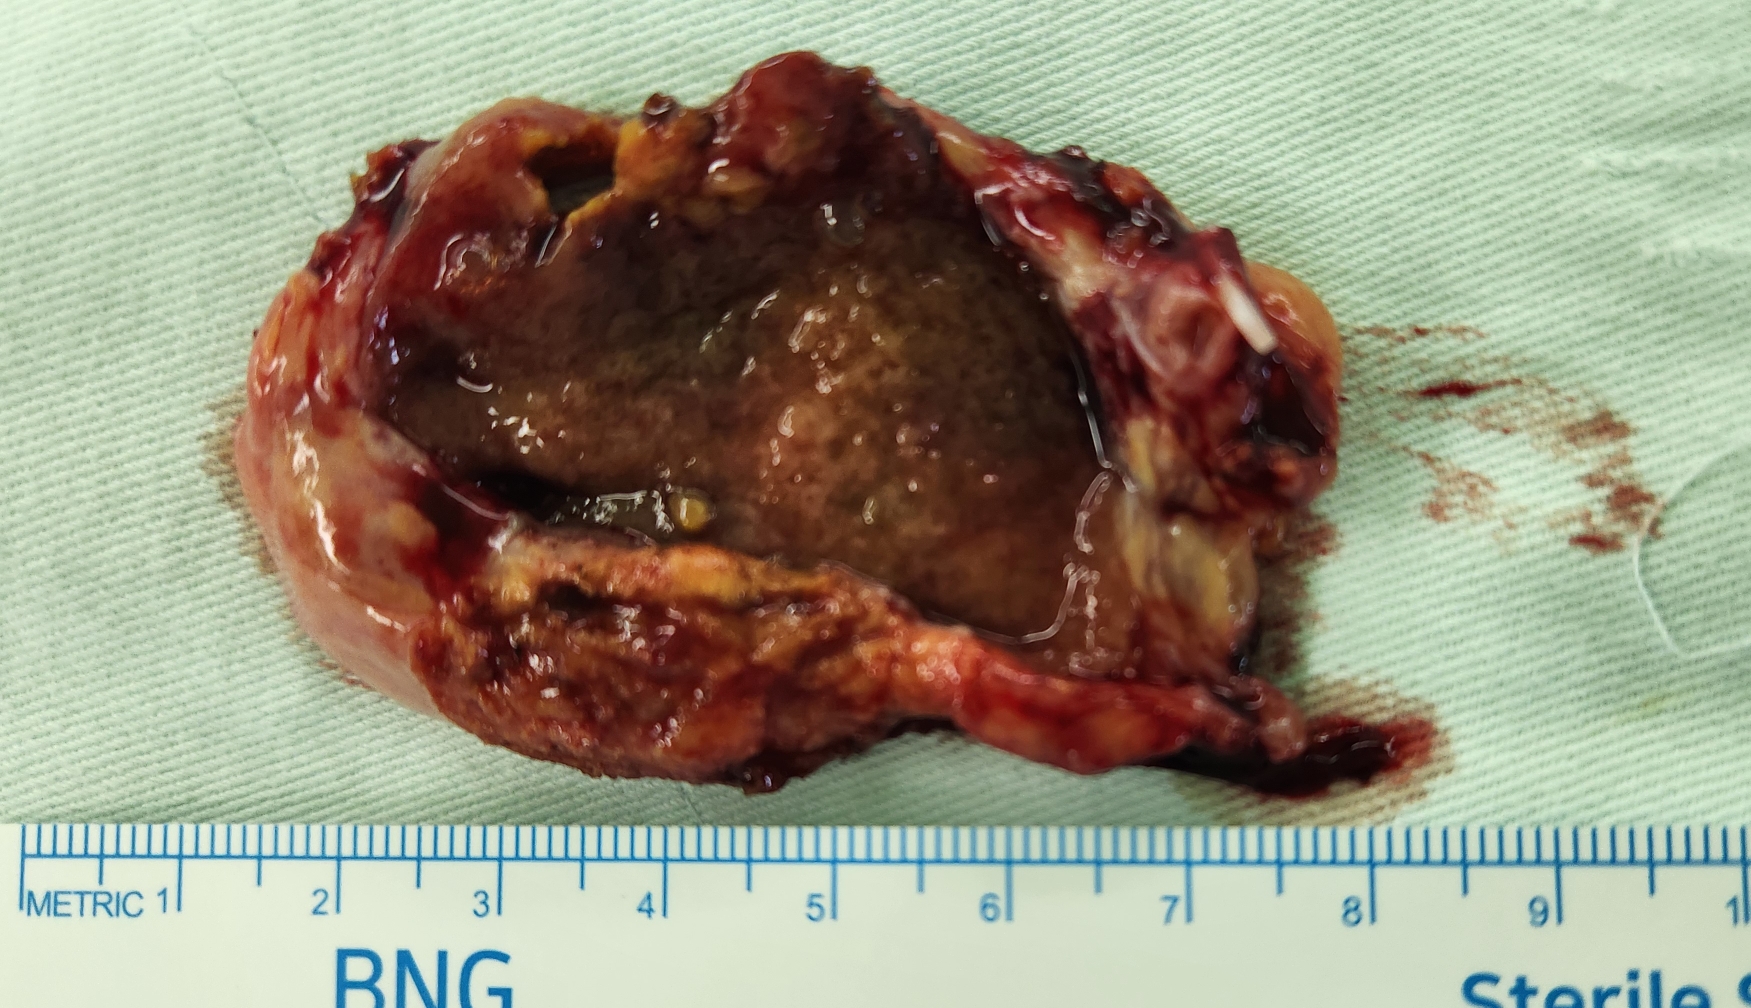

상복부통증으로 경북대병원에서 2달전 총담관결석 및 급성 담낭염으로 진단후 PTGBD 삽입하고 ERCP 시행하여 스텐트 시술 하였고 담낭절제 위해 제게 오신 분입니다.

방금 복강경 담낭절제술을 시행했습니다.

수술은 25분 걸렸습니다.